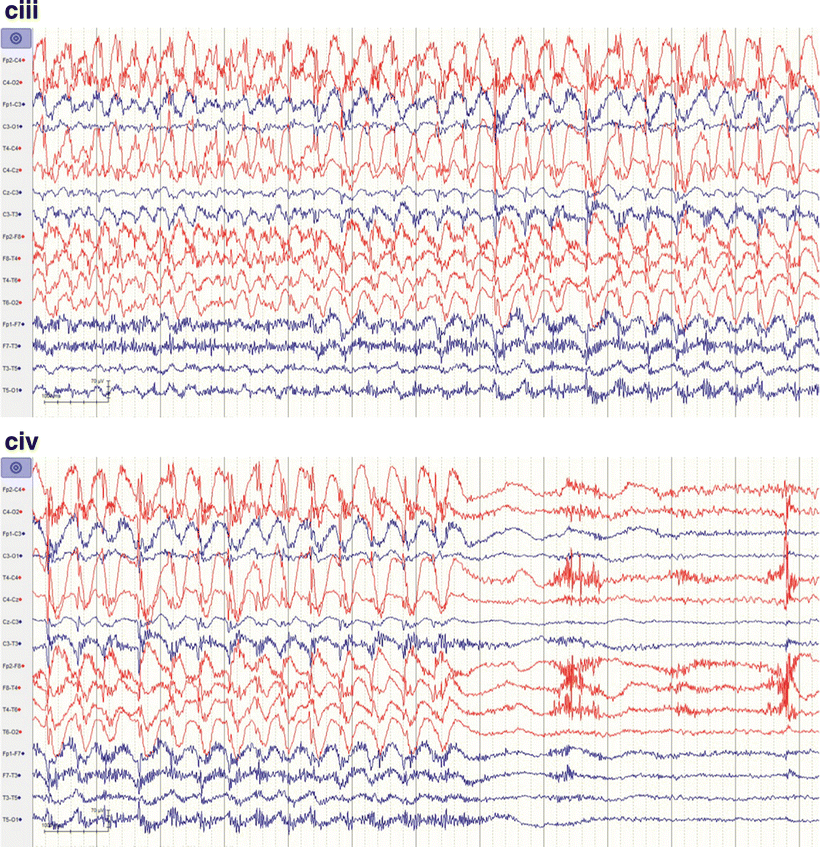

Continuous 17hour video eeG monitoring. Notes The eeG was collected Continuous Eeg Monitoring It covers indications, patient populations, technical. Explains the use and interpretation of continuous eeg (ceeg) monitoring in critically ill patients; Guidelines and recommendations for effective monitoring. Continuous eeg (ceeg) monitoring is paramount in critically ill patients,. Continuous electroencephalogram (ceeg) monitoring is increasingly being used for brain monitoring in neurocritical care setting. This article provides expert recommendations on the use of. Continuous Eeg Monitoring.